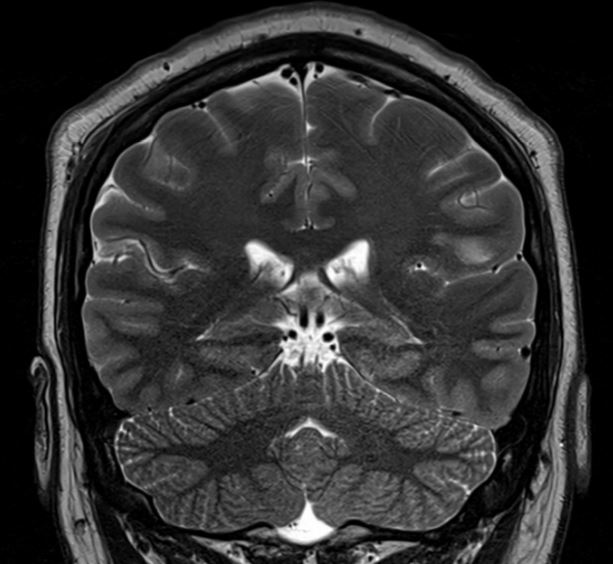

The MRI demonstrates a juxta-cortical, linear lesion in the white matter of the left post central gyrus extending medially to above the insular cortex. There is no mass effect and no enhancement. The nature of the lesion is unclear and does not relate to any of his symptomatology. His loss of consciousness almost certainly was related to a very large binge on alcohol, with very high blood alcohol levels. There is no history of any right facial or any other sensory symptomatology, nor of any episodic or persistent language dysfunction. There is no history of previous cranial trauma. His perinatal and developmental history is unremarkable.

In addition to the above lesion there are a few other punctate white matter lesions. It is presumed that these are old and have been discovered coincidentally as they do not relate to any past or recent symptomatology and are therefore "asymptomatic". I discussed the case with experienced neuroradiologist who reports that the lesions appear "innocuous".  The case also makes the point that diagnostic tests may result in a lot of harm; in this instance the patient was effectively "medically deported" within 24 hours of the scan having been done in a highly developed country. If the EEG is misinterpreted, the patient's problems will only be compounded. His EEG was normal for 72 hours; the rationale for performing it for this duration will be discussed at a later stage